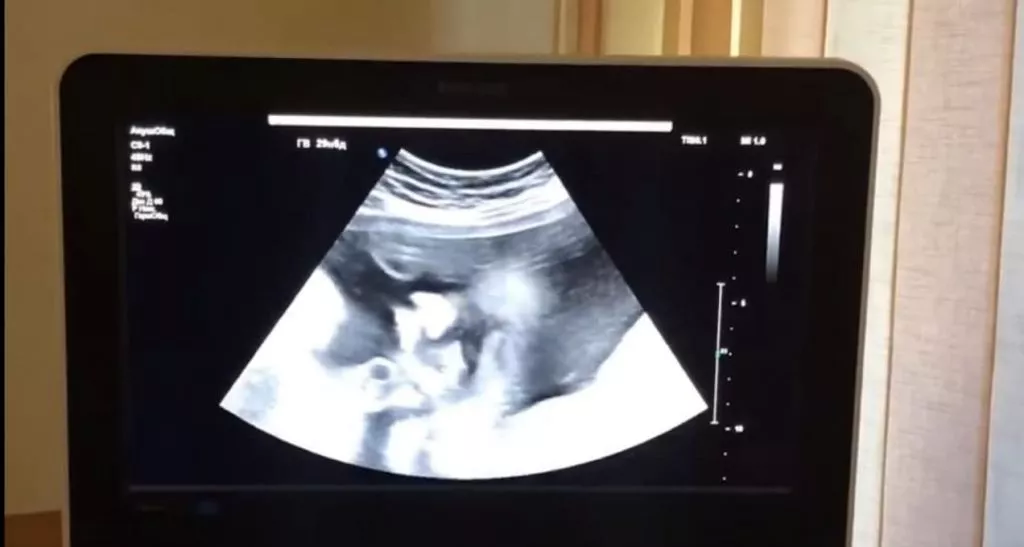

Іваничівська багатопрофільна лікарня отримала нове медобладнання від Німеччини, вартістю майже півтора мільйони гривень. Медзакладу передали сучасний ультразвуковий пристрій Mindrey DC-60 Expert з набором датчиків. Його лікарня отримала в рамках німецько-українського проекту «Пакет солідарності громад при ...

У відділенні функціональної діагностики КНП «НЦМЛ» пацієнти мають змогу пройти усі обстеження безплатно за направленням від лікаря. У Волинській області є чотири найсучасніших УЗД апарати, один з них - в Нововолинській центральній міській лікарні, повідомляють у фейсбуці установи. Як зазначають, пацієнт може отримати ...